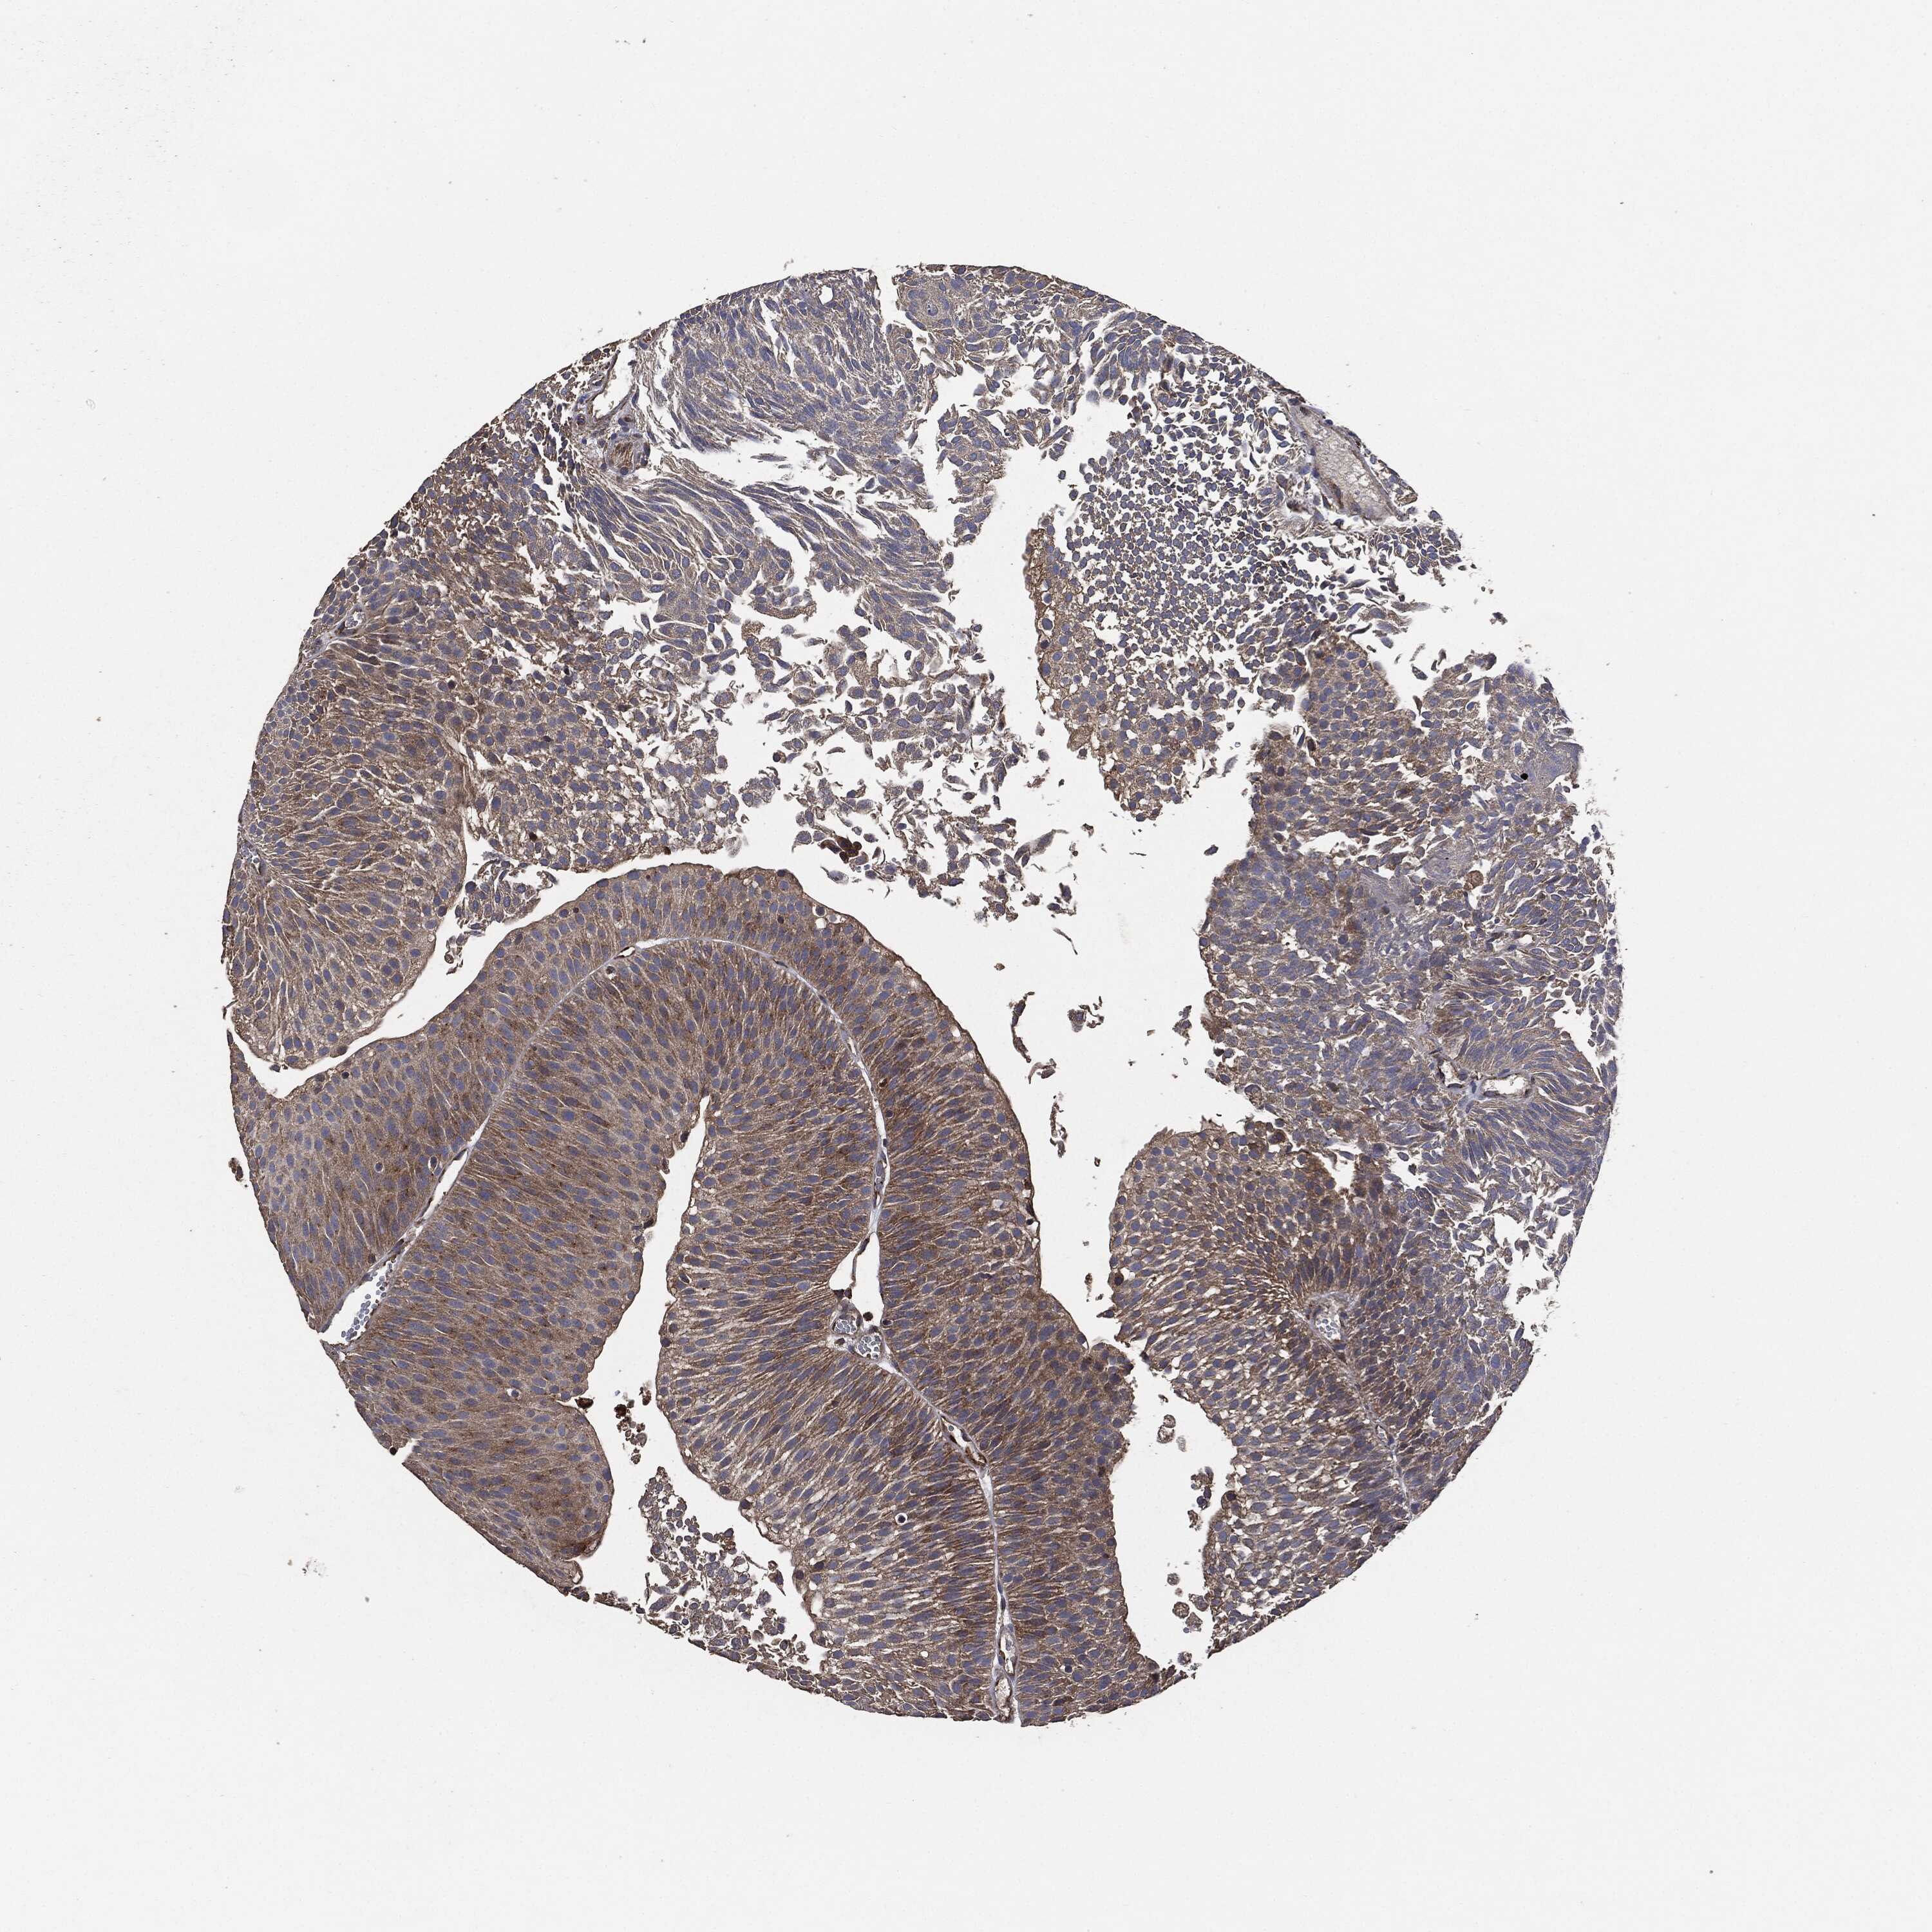

UROTHELIAL CANCER - Protein expressioni

A mouse-over function shows sample information and annotation data. Click on an image to view it in a full screen mode. Samples can be filtered based on level of antibody staining by selecting one or several of the following categories: high, medium, low and not detected. The assay and annotation is described here.

Antibody stainingi

Antibody staining in the annotated cell types in the current human tissue is reported as not detected, low, medium, or high, based on conventional immunohistochemistry profiling in selected tissues. This score is based on the combination of the staining intensity and fraction of stained cells.

Each image is clickable and will lead to virtual microscopy that enables deeper exploration of all samples and also displays staining intensity scores, fraction scores and subcellular localization as well as patient and tissue information for each sample.

Antibody HPA073281

Antibody CAB025316

Staining

High

Medium

Low

Not detected

Intensity

Strong

Moderate

Weak

Negative

Quantity

>75%

75%-25%

<25%

None

Location

Nuclear

Cytoplasmic/membranous

Cytoplasmic/membranous,nuclear

Urothelial carcinoma, Low grade